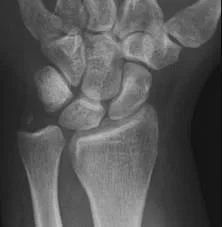

Surgical Neck- Problem

- If osteoporotic bone

- Difficult fixation

- Possible associated injury to Axillary nerve

- Motor: Deltoid

- Sensory: upper lateral arm